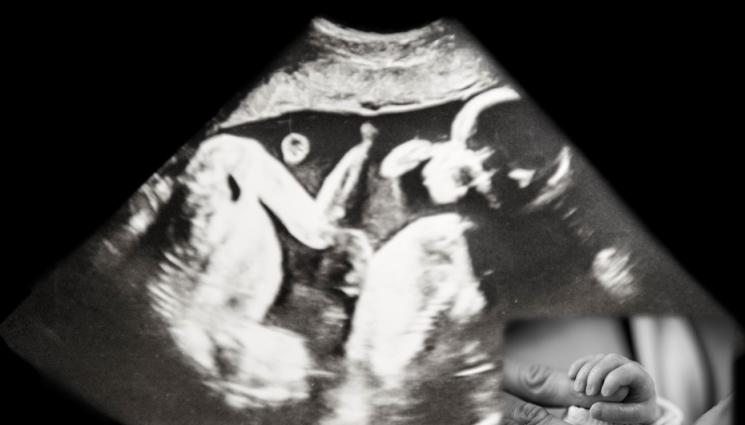

Б олницата "Ихилов" в Тел Авив съобщи, че жена с две матки е родила две близначета - по едно във всяка, предаде ДПА. Така бебетата са се "срещнали" чак след раждането. Жената, която е на 31 години, е родена с двойна матка. При това състояние обичайната матка е разделена в средата. Раждане на близначета в такива случаи е извънредно рядко. Вероятността е около едно на милион. Бременността е наблюдавана много отблизо, защото е била с висок риск. Раждането е било със секцио през 35-ата седмица.

Жената е научила за двойната си матка, когато е била на 20 години. Преди да забременее, тя се е притеснявала, че бебето ще се имплантира в дясната й по-малка матка. Животът обаче й поднесъл нещо друго. При първия преглед за установяване на бременността лекарят почти припаднал. "Необходими му бяха почти 10 минути, преди да успее да ми каже, че има ембрион и в двете матки", спомня си младата майка. През бременността жената много се притеснявала, но сега близнаците - момче и момиче "са сладки и страхотни". Тя е убедена, че те ще бъдат приятели.